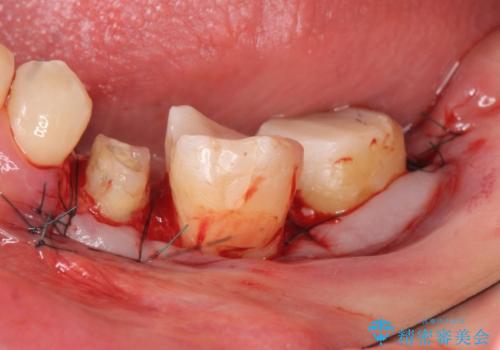

- 左下の奥歯がズキズキ痛むので診て欲しいといらっしゃった方の症例です。他院では5番目と7番目の歯を抜歯してインプラントと言われたが、出来れば歯を残したいとのことでした。

痛みの原因は6番目の虫歯であること、5番目、6番目の歯は歯茎より深い虫歯であり現状では保存が難しいことを説明した上で、歯を挺出させる部分矯正と歯茎を下げる歯周外科を行いました。

手術後歯茎の治癒を待ち、オールセラミッククラウンによる補綴を行いました。